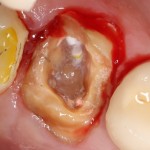

Удаление зубов у пациентов, принимающих бисфосфонаты.

Во-первых, само удаление должно быть максимально аккуратным и щадящим. Как это сделать — читайте здесь>>, тут есть очень полезная и доступная статья.

Во-вторых, максимальное сохранение окружающей десны зуб — это наше всё. Если в процессе удаления разорвать десну на британский флаг, то, как нам подсказывает доктор Ясенхуй, о герметичном ушивании лунок можно забыть. Поэтому удаление зубов проводится методом фрагментации и с предварительным удалением коронковой части — так лучше видно десну и меньше шансов её повредить.

Нужно следить за тем, чтобы опилки от пломб, коронок и самих зубов не попали в лунки.

Далее — разрез. Он всегда более обширный, нежели при обычном удалении зубов, поскольку слизистую для ушивания лунки нужно мобилизовать. Намного удобнее проводить разрезы и формировать лоскуты до удаления корней зубов, сразу после «отпиливания» коронковых частей».

Корни зубов удаляются всё тем же методом фрагментации. Так, чтобы стенки лунки остались целыми. Как это сделать — написано тут>>.

После удаления корней зубов нужно резецировать и сгладить все острые края лунок, которые могут прорезаться в процессе заживления. И конечно же убрать все подвижные фрагменты кости, если таковые имеются.

Операция заканчивается ревизией лунок, заполнением их специальными препаратами и наложением швов. Операционная рана наглухо ушивается нерезорбируемым монофиламентным шовным материалом.